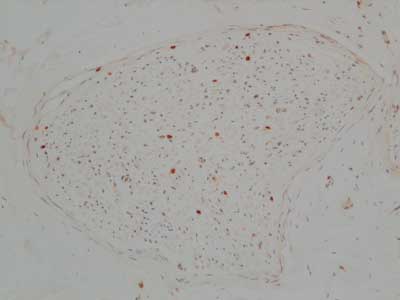

A right sural nerve biopsy showed severe loss of myelinated nerve fibres, and many of the surviving fibres showed varying stages of axonal degeneration (Box 1) associated with a sparse, patchy endoneurial mononuclear cell infiltrate in some fascicles and prominent endoneurial fibrosis on trichrome stain. The CD45RB immunostain showed increased numbers of immunopositive endoneurial lymphoid cells that showed immunopositivity with the T-cell markers CD3 (Box 2) and CD5. The CD68 immunostain showed increased endoneurial macrophages, and ultrastructural assessment confirmed macrophage phagocytosis of degenerate myelinated fibres. CD20 immunostain was negative. The Congo red stain for amyloid was negative. A TCRγ clonality study of the nerve biopsy showed a monoclonal band identical to the previous band detected in the duodenal biopsies, confirming infiltration of the nerve by T-cell lymphoma (Box 3).